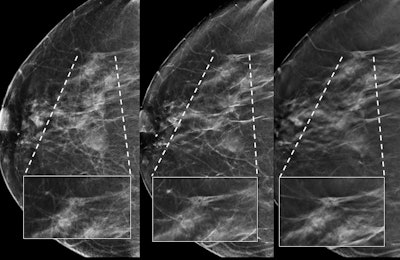

The researchers also compared detected cancers and recalls between double 2D and single reading of DBT (third and fourth readings) to assess the single reading as a new screening strategy, and they compared double 2D and double reading of DBT to evaluate whether the availability of 2D mammography improved the outcomes of DBT.

Regarding cancer detection, comparing double 2D with the third reading, the researchers found 69 cancers were detected at both 2D and the third reading. Seven cancers were detected only at double 2D compared with 18 detected only at the third reading, which resulted in an increase in cancer detection of 12.6% at the third reading.

Comparing double 2D with the fourth reading, they found 65 cancers were detected with both techniques, 11 cancers were detected only at double 2D compared with 16 detected at the fourth reading, resulting in an increase in cancer detection of 6.2%.

Lastly, when comparing the fourth reading with the third reading, they found 76 cancers were detected at both readings. Five cancers were detected only at the fourth reading compared with 11 detected at the third reading, meaning an increase of 6.9%.